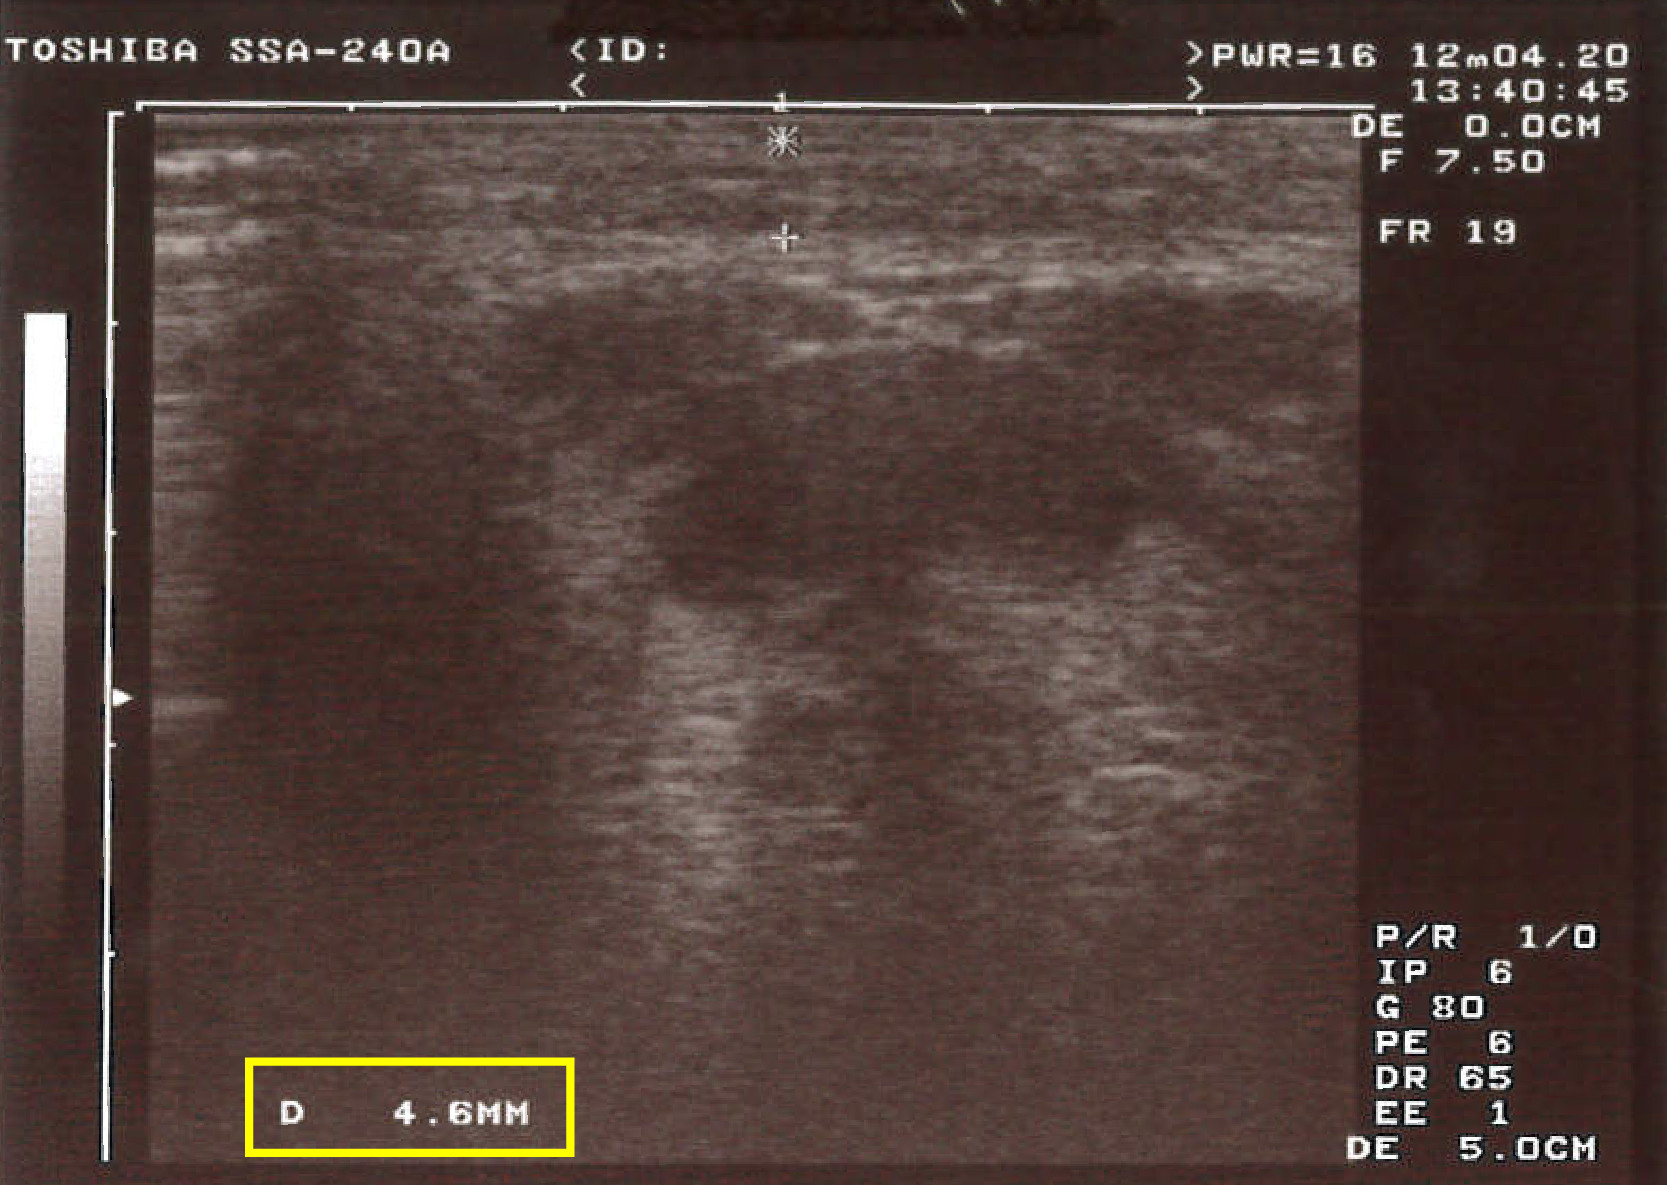

【超音波測脂 術後1個月】

一個月回診看術前、術後對比照,

OMG 真的有差!我其實只打一劑,

就已經減少 0.4 mm 厚度的脂肪呢 ~